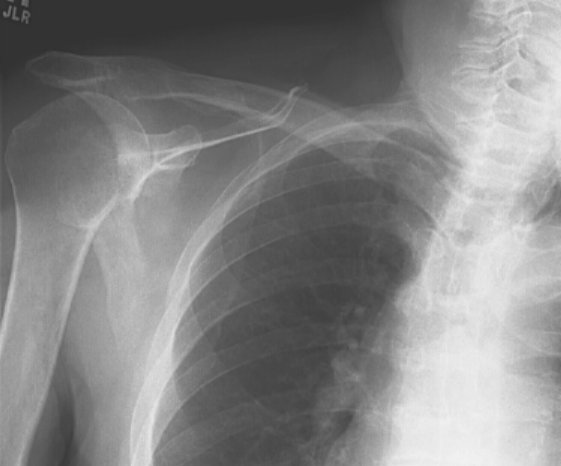

Return to Anterior Dislocation (Humerus)